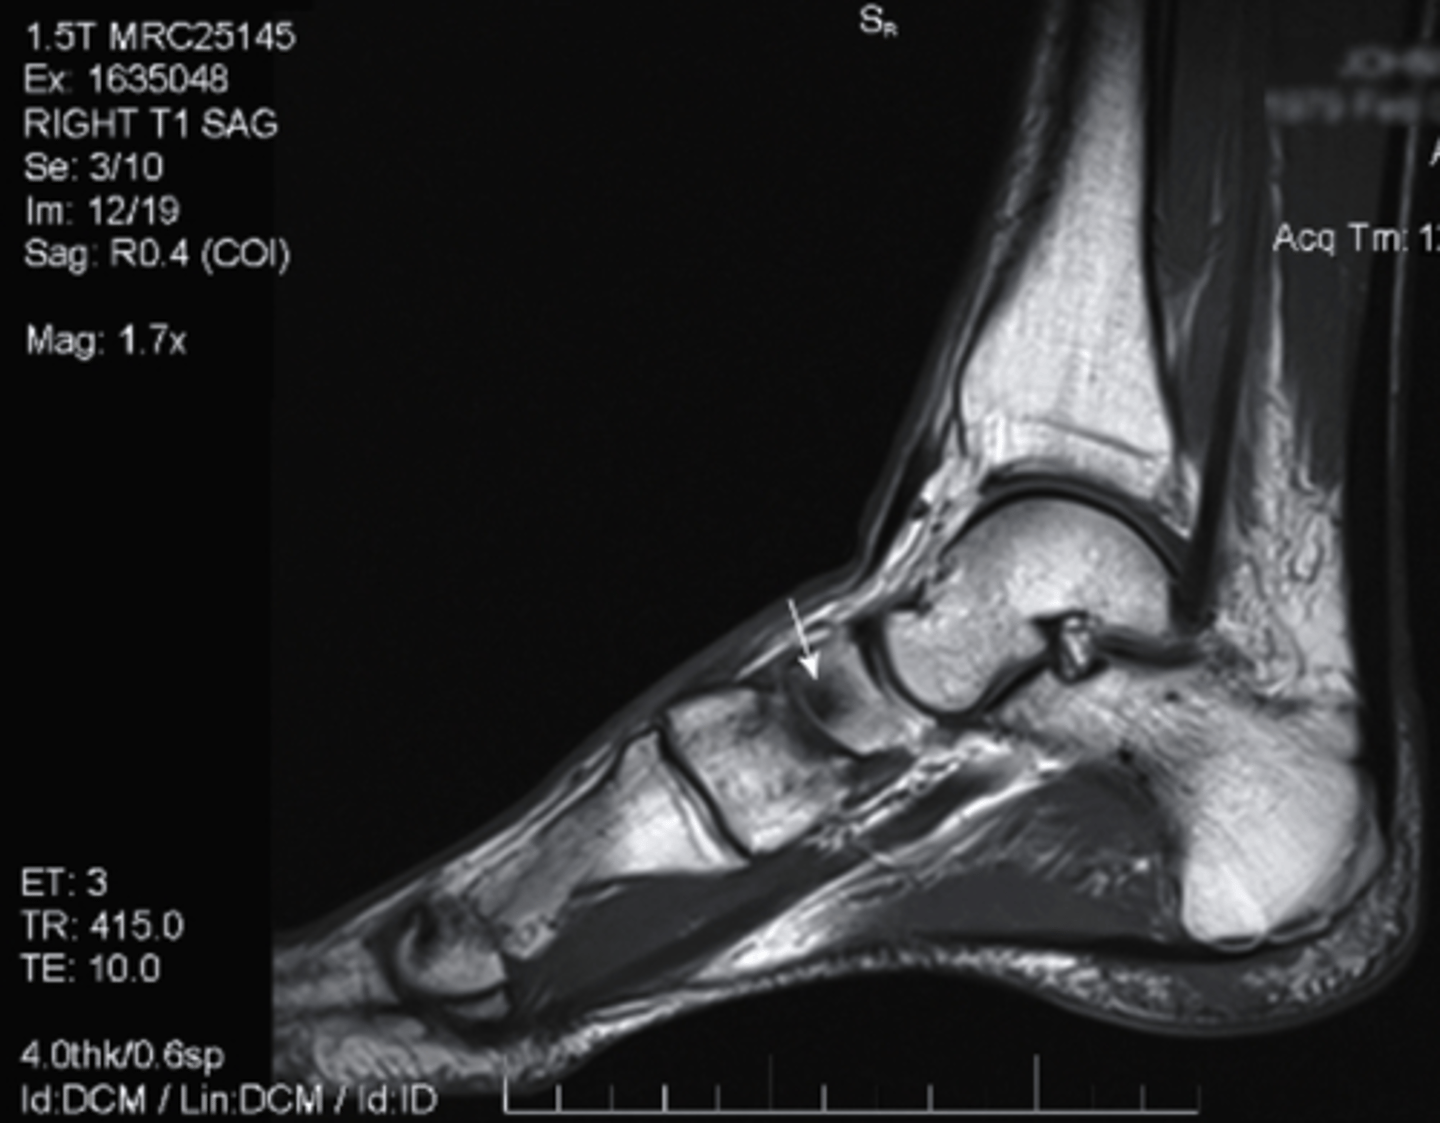

T1 MRI

what type of imaging is this?

a. T2 MRI

b. CT Scan

c. Radiograph

d. T1 MRI